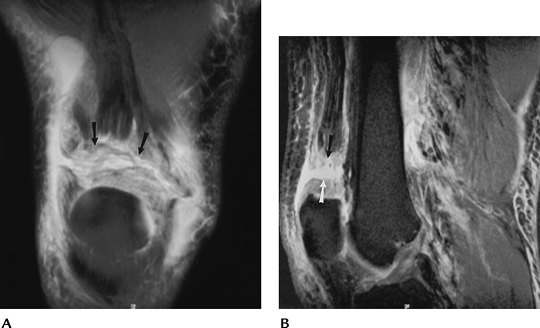

Patellar Disorders: Patellar Tracking And Instability

Position of the patella in relation to

Conditions include

Lateral subluxation—lateral translation of the patella so the facet extends beyond the articular margin of the condyles

-

Excessive lateral pressure syndrome—lateral facet joint narrowed or patella tilted without subluxation

Medial subluxation—medial translation of the patella so the facet extends beyond the medial condyle

Dislocation—complete loss of articular interfaces

Imaging can be accomplished with axial

or MR techniques to image the patellofemoral relationships through

![]() |

FIGURE 5-51 Patellar views of both knees showing lateral tilt without subluxation because of lateral pressure syndrome.

P.273

|

FIGURE 5-52 Axial gradient echo image demonstrating lateral subluxation and a tear (arrow) of the medial retinaculum.

FIGURE 5-53 Sagittal (A) and axial (B)

T2-weighted MR images after patellar dislocation with fluid–fluid levels, retinacular tear, and shaving of the patellar articular cartilage (arrow). |